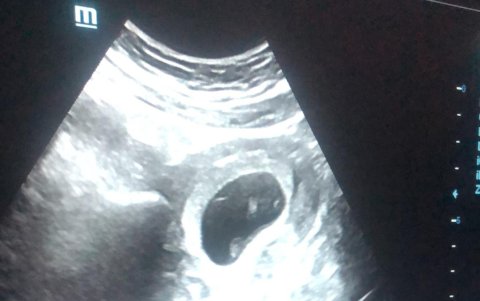

Ecografía del bebé.